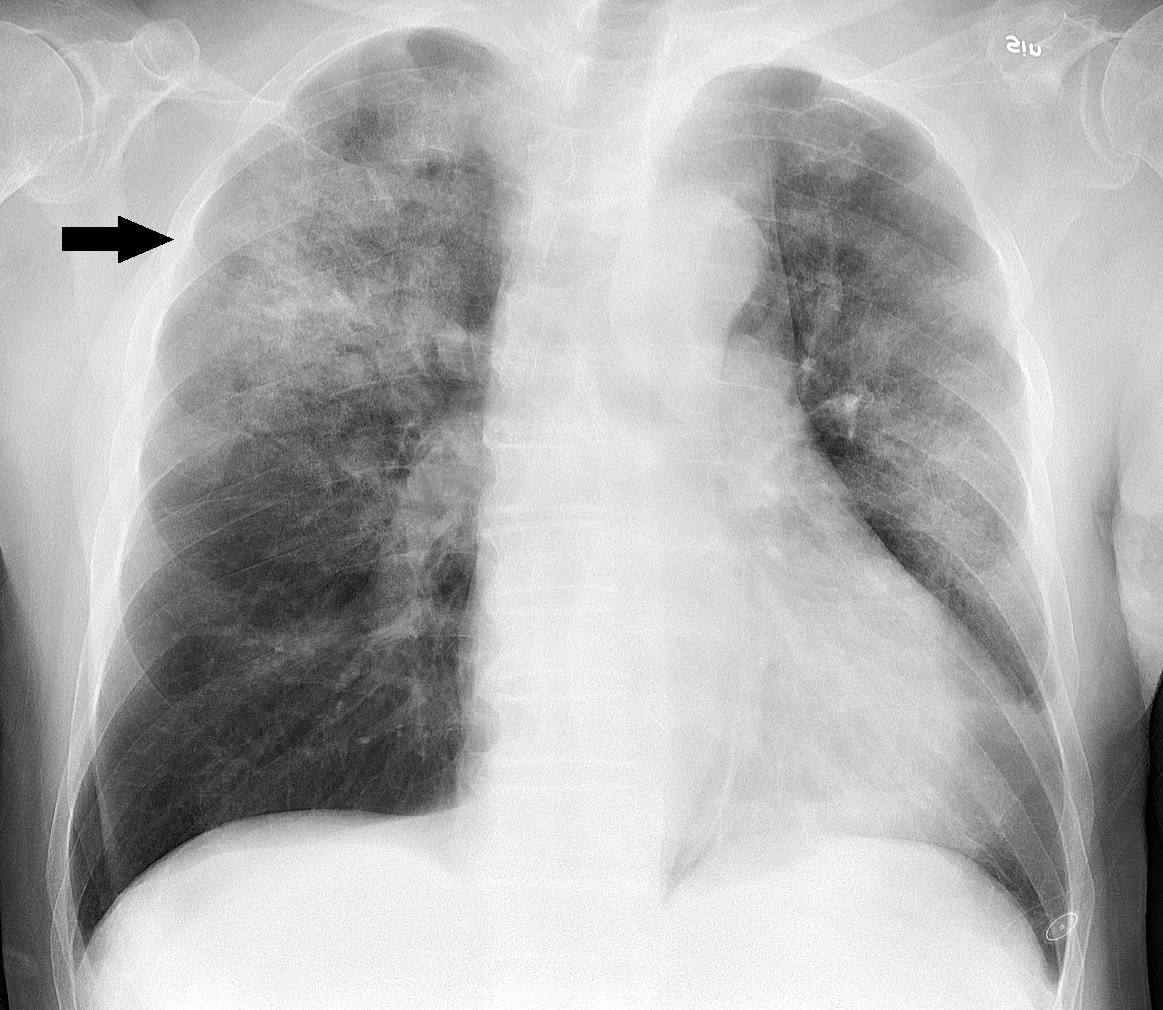

폐렴이 의심되면 흉부 X-선 검사로 진단을 내리는데

흉부 X-선 검사는 병이 얼마나 퍼졌는지도 보여줍니다.